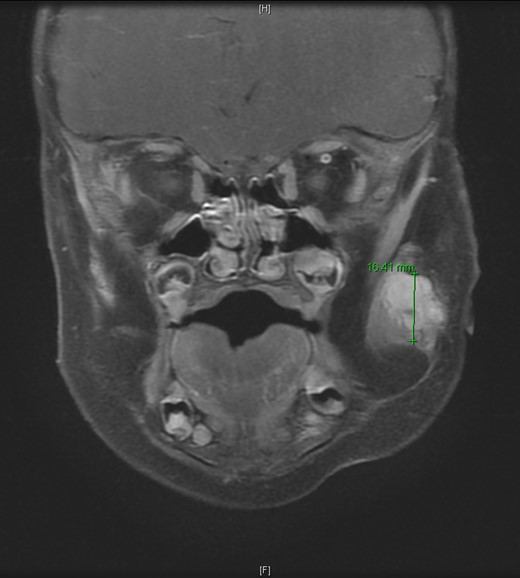

An 11-month-old male with a history of nasolacrimal duct stenosis and 4 mm thyroglossal duct cyst presented for evaluation of left facial swelling for 9 months. Approximately 6 months prior to admission, a mass was identified on the left cheek which had progressively increased in size over the past 2 months. The patient also had intermittent fevers the week prior to admission but was otherwise healthy. Baseline labs, including platelets, were within normal limits. On exam, he was found to have a firm, mobile, non-tender mass just inferior to the left zygomatic arch. Ultrasound revealed a vascularized solid lesion measuring 12 mm × 15 mm × 16 mm limited to the superficial soft tissues. MRI showed a multi-lobular mass with increased T2 signal centered within the left masseter and infiltrating signal in surrounding subcutaneous tissue (Fig. 1). The patient subsequently underwent ultrasound-guided core biopsy. The initial pathological diagnosis was consistent with TA, showing fibrovascular tissue containing compact nests of variably sized and ill-defined vascular channels. Immunohistochemistry staining showed the endothelial cells to be diffusively reactive for CD34 and CD31, partially reactive for D2-40, and negative for GLUT-1. However, upon further review, KHE was favored given the solid and infiltrative components on MRI, normal overlying skin on exam, and location of the lesion within subcutaneous fat. Accordingly, low-dose daily aspirin was prescribed prophylactically to prevent KMP. An MRI 2 months later, along with serial ultrasound images in the ensuing 26 months, showed no further growth (Fig. 2). His parents noted intermittent painless changes in size that did not seem to be related to any stimulus and returned to baseline size within hours. Surgical intervention at 3 years old is anticipated.

T2-weighted MRI revealed a homogenously enhancing 13 mm × 11 mm × 16.4 mm mass with indistinct margins centered within the left masseter muscle and protruding into the subcutaneous tissues laterally.

T2-weighted MRI 2 months later revealed a 14.5 mm × 14.1 mm × 15.95 mm mass partially involving the masseter muscle with no internal vascular flow voids.